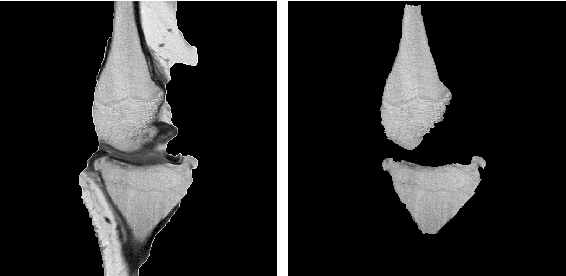

Abstract:Image segmentation is often performed on medical images for identifying diseases in clinical evaluation. Hence it has become one of the major research areas. Conventional image segmentation techniques are unable to provide satisfactory segmentation results for medical images as they contain irregularities. They need to be pre-processed before segmentation. In order to obtain the most suitable method for medical image segmentation, we propose a two stage algorithm. The first stage automatically generates a binary marker image of the region of interest using mathematical morphology. This marker serves as the mask image for the second stage which uses GrabCut on the input image thus resulting in an efficient segmented result. The obtained result can be further refined by user interaction which can be done using the Graphical User Interface (GUI). Experimental results show that the proposed method is accurate and provides satisfactory segmentation results with minimum user interaction on medical as well as natural images.